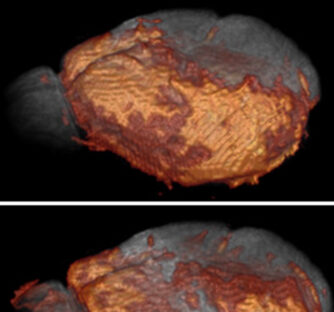

Controled delivery of mAb to the mouse brain using focused ultrasound and immunoTEP